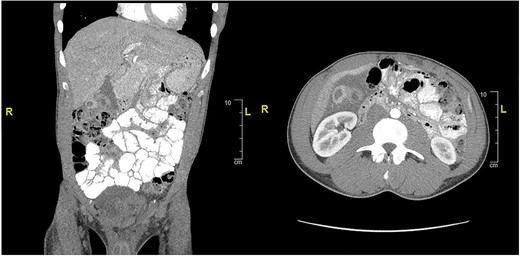

CT of abdomen and pelvis showing peripherally hyperdense septated collection within the porta hepatis with surrounding fluid signal attenuation likely representing an abscess seen around the gallbladder.